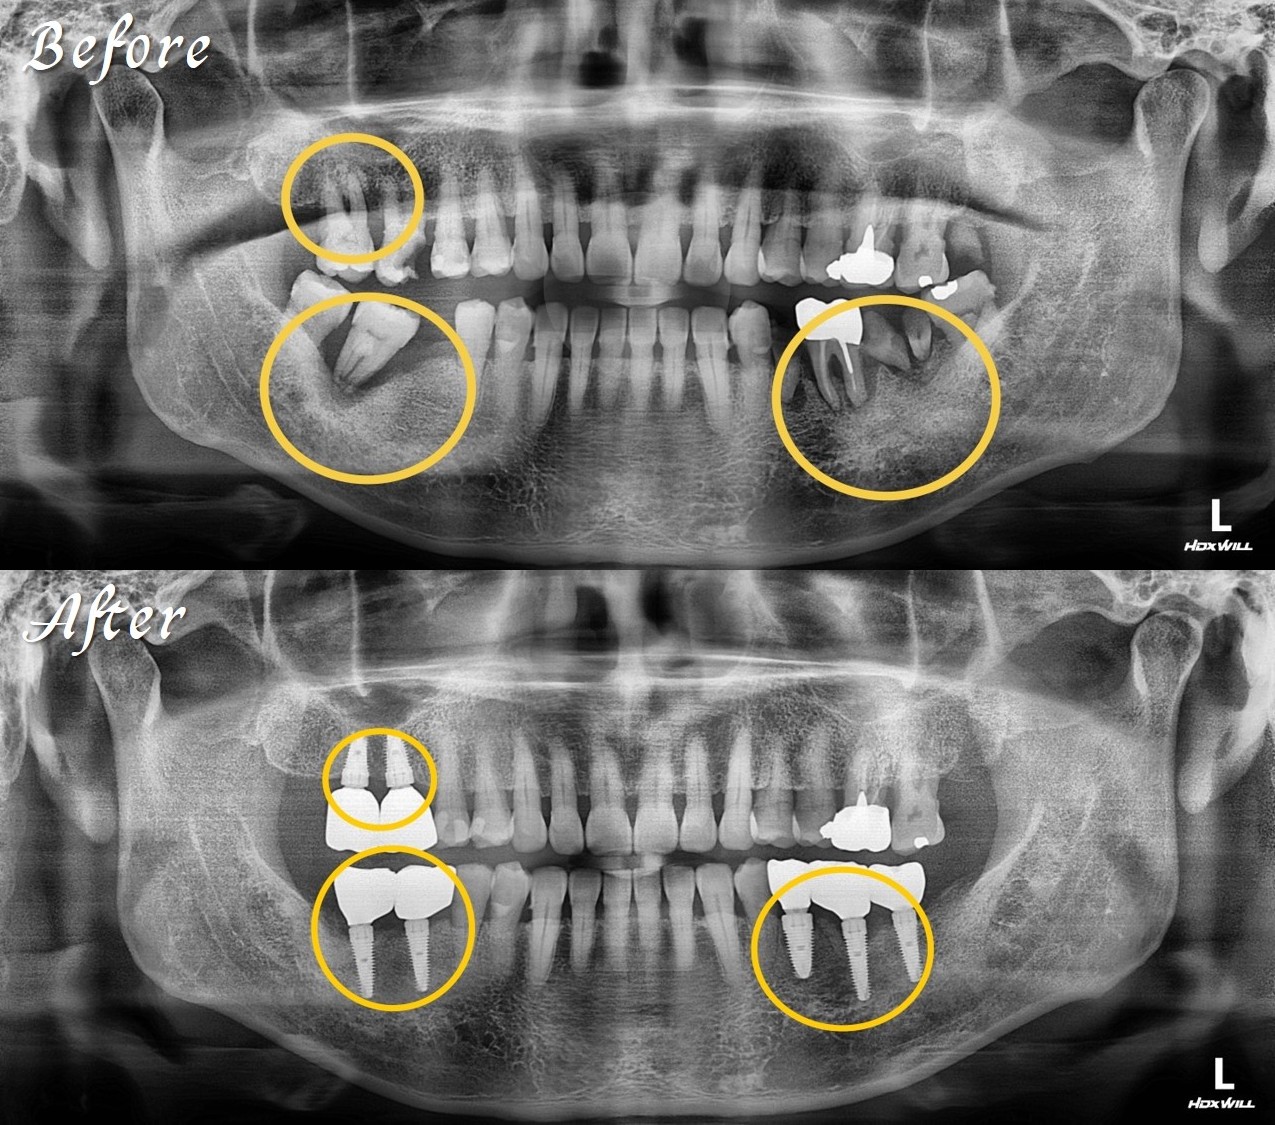

精奈創一鑽植牙系統團隊|嚴重牙周病案例

這是一個嚴重牙周病的案例,陳博士在30分鐘內完成即拔即植與補骨手術,同時做到水平與垂直補骨一次到位,並在4個月後完成永久假牙裝戴,恢復咬合與生活品質。

陳博士使用精奈創5合一植牙技術,不但將嚴重牙周病的牙齒拔除、同時植入植體和補骨一次完成,大大的減少療程時間與手術次數,當天就有臨時固定假牙可以進食,生活作息完全不受影響。